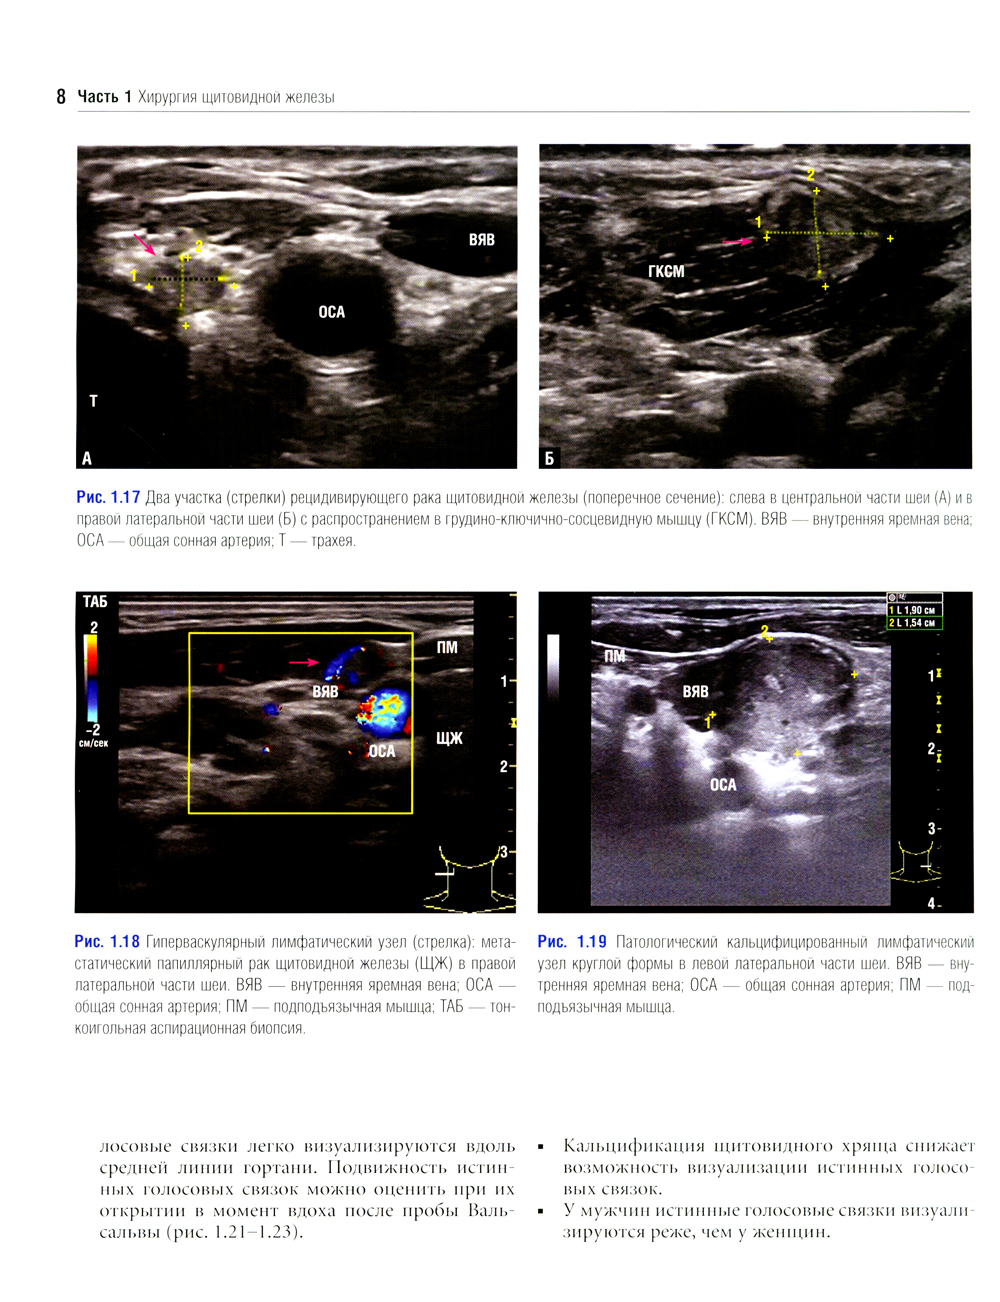

Данное издание представляет собой великолепно иллюстрированный хирургический атлас. В нем рассмотрены методы ультразвукового исследования шеи, молекулярно-генетическое тестирование пациентов с узловыми образованиями в щитовидной железе, робот-ассистированные хирургические методы, техника эндоскопических операций при эндокринных опухолях, хирургия при рецидиве заболевания, аутотранснлантация и криоконсервация околощитовидных желез, адреналэктомия при метастазе в надпочечнике, хирургия нейроэндокринных опухолей тонкой кишки и их метастазов в печени. «Атлас эндокринной хирургии» состоит из 4 частей: «Хирургия щитовидной железы», «Хирургия околощитовидных желез», «Хирургия надпочечников», «Хирургия опухолей поджелудочной железы и карциноидов». Всего в издании 29 глав, подготовленных сотрудниками экспертных факультетов ведущих медицинских школ США, Европы и Азии. Каждая глава состоит из разделов, в которых описаны общие сведения, показания и противопоказания, оценка риска, алгоритм принятия решений и планирование вмешательства, необходимое оборудование и материалы, хирургические техники, результаты лечения, осложнения и последующее наблюдение, а также даны советы и предостережения авторов. В книге много информации, которой нет в других источниках. Наряду с многочисленными фотографиями, сделанными в ходе операций, а также данными, полученными при различных методах визуализации, приведено значительное количество иллюстраций и видеоматериалов, демонстрирующих хирургическую технику или обследование. Издание предназначено практикующим врачам в области эндокринной хирургии, специалистам в смежных областях медицины и студентам медицинских высших учебных заведений.| Издательство | Логосфера |